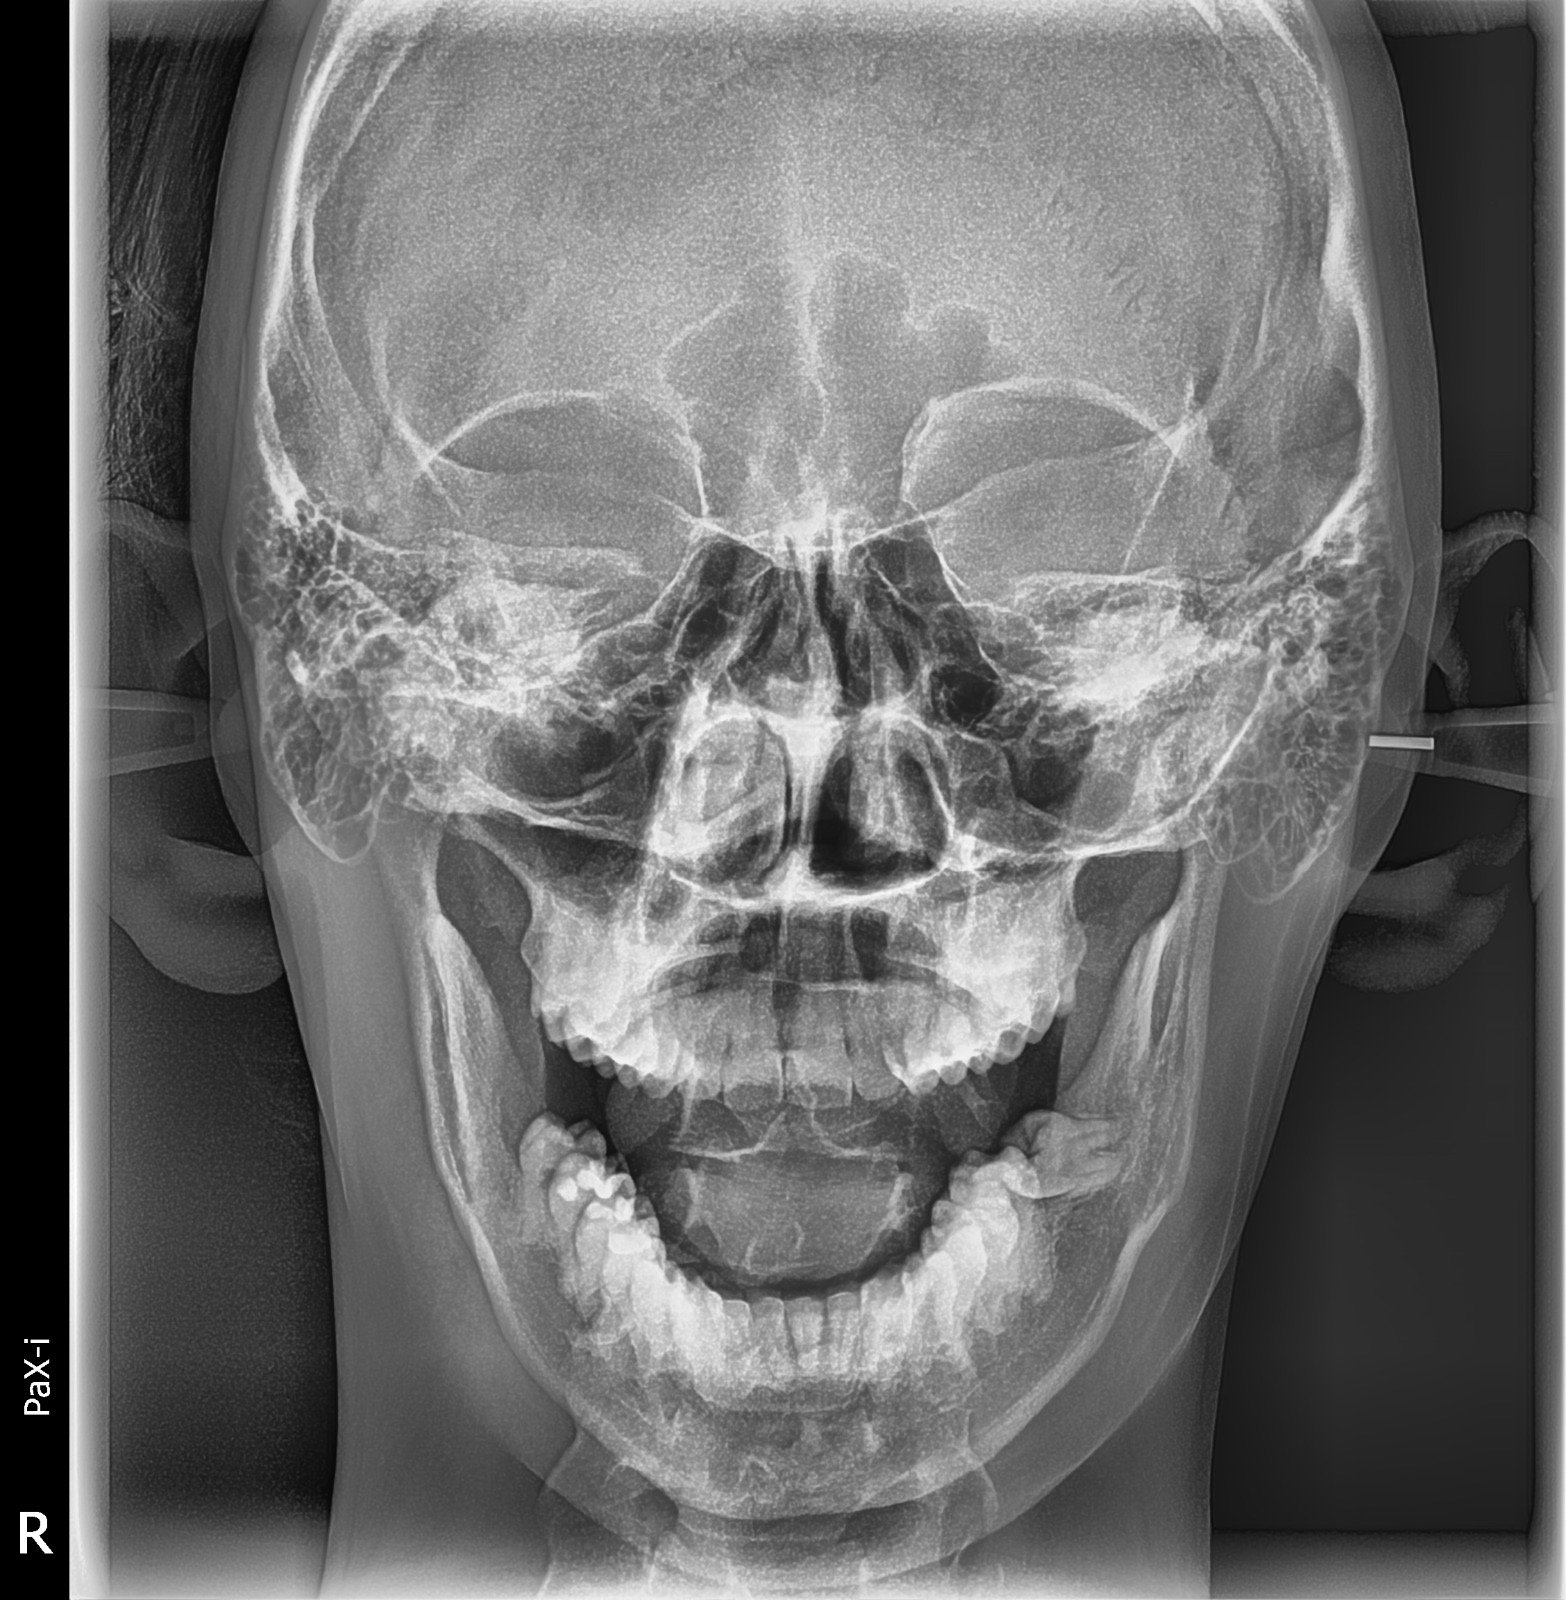

Imagen de Rx Postero-Anterior

Rx Postero-Anterior

la rx postero-anterior analiza estructuras faciales,senos paranasales o huesos del cráneo

Costo: Consultar precio Duración: 10 min